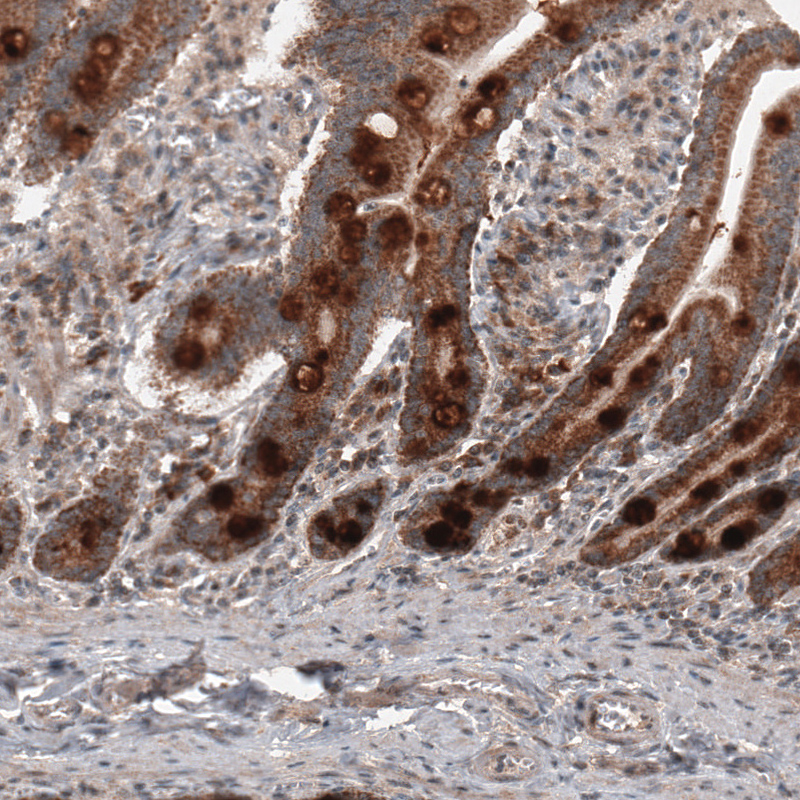

Immunohistochemical staining of human duodenum shows strong cytoplasmic immunoreactivity in glandular cells.